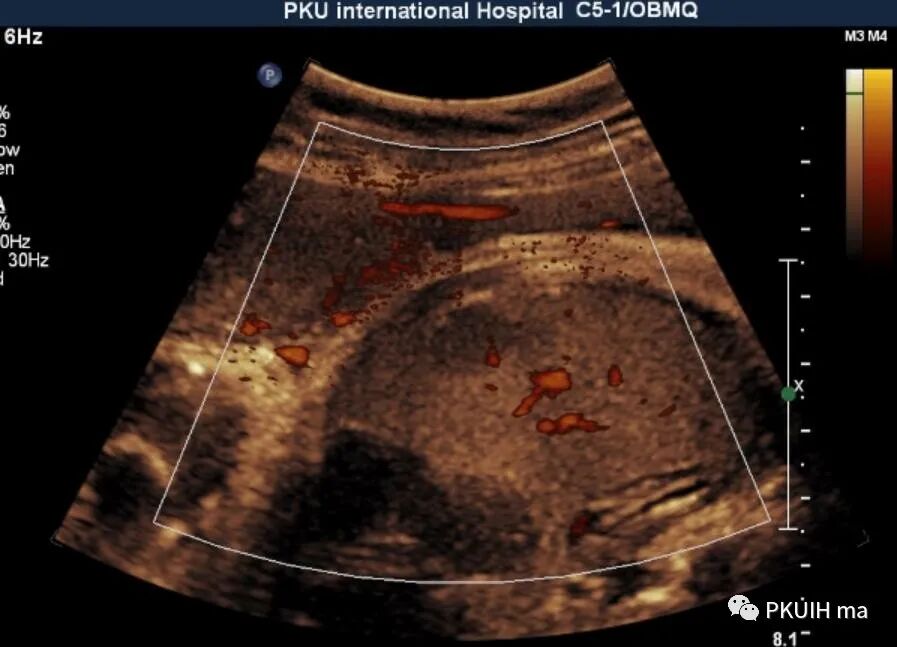

CDFI内血流不明显,用CDE发现结节内见少许血流信号

胎儿期肝脏占位很少见,超声能发现的更少见。胎儿肝脏最常见的良性肿瘤是血管瘤、其次是错构瘤,恶性肿瘤是肝母细胞瘤。肝血管瘤较小时表现实性低回声,边界清或尚清,内回声均匀,较大时多成囊实性,内回声不均,部分可呈蜂窝样,边界多不清晰。CDFI:小的肿瘤血流不明显,大的肿瘤血流丰富。诊断主要依靠超声或MRI,但胎儿期对于小的肿瘤往往容易漏诊,尤其是晚孕期才出现的肿瘤。

肝母细胞瘤为原发性恶性肿瘤,生长迅速,进展快。超声表现多样化,可可为低回声、高回声或混合回声,以低回声多见,边界相对清晰,肿瘤较大可有坏死、钙化等。CDFI:血流信号相对血管瘤少,内仅见少许血流信号。肿瘤较小时很难和血管瘤鉴别。